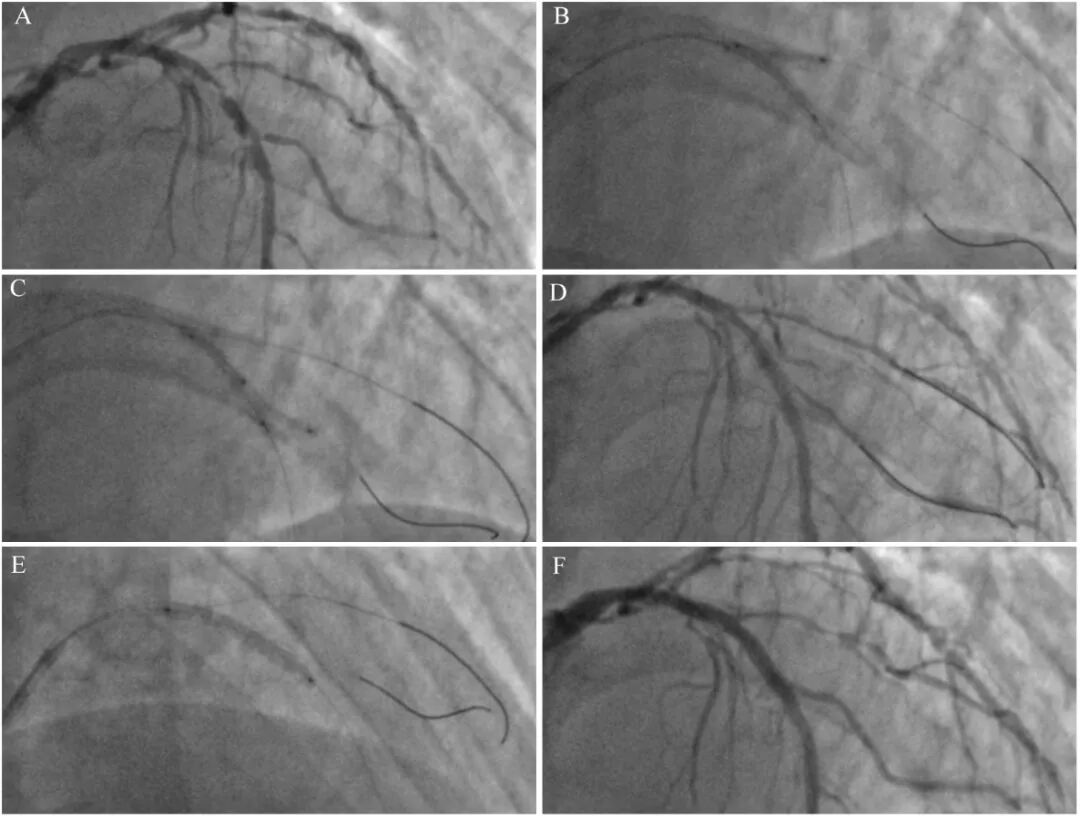

球囊预扩张可通过斑块的纵向或横向移位、脊移位、血管壁向外移位等机制(简称三大移位机制)扩大分支开口空间。但在支架置入阶段,主支支架可促进斑块反向移位、脊反向移位,从而在很大程度上抵消了球囊预扩张的作用(图1)。因此保护分支的效果远不如球囊拘谨[2]。

图1分支球囊预扩张的作用机制和局限性